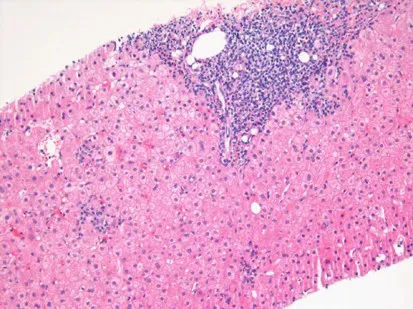

Chronic Complications - The Liver's Long Road

- Cirrhosis & Decompensation: Develops in ~20% of patients over 20-30 years, leading to portal hypertension and hepatic failure (ascites, variceal bleeding, encephalopathy).

- Hepatocellular Carcinoma (HCC): Significantly ↑ risk, especially with established cirrhosis. Regular surveillance with ultrasound is recommended.